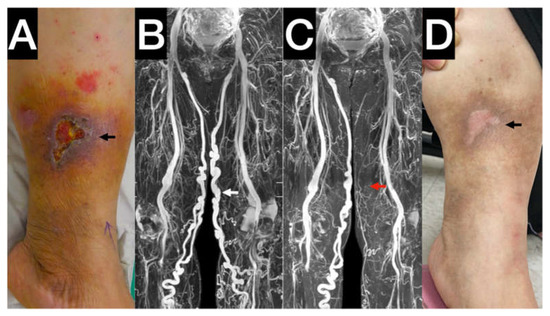

- Chen, C.W.; Tseng, Y.H.; Wong, M.Y.; Wu, C.M.; Lin, B.S.; Huang, Y.K. Stasis Leg Ulcers: Venous System Revises by Triggered Angiography Non-Contrast-Enhanced Sequence Magnetic Resonance Imaging. Diagnostics 2020, 10, 707. [Google Scholar] [CrossRef]

- Chen, C.W.; Fang, Y.F.; Tseng, Y.H.; Wong, M.Y.; Lin, Y.H.; Hsu, Y.C.; Lin, B.S.; Huang, Y.K. A Novel Tool for a Challenging Disease: Stasis Leg Ulcers Assessed Using QFlow in Triggered Angiography Noncontrast Enhanced Magnetic Resonance Imaging. J. Pers. Med. 2021, 11, 857. [Google Scholar] [CrossRef]